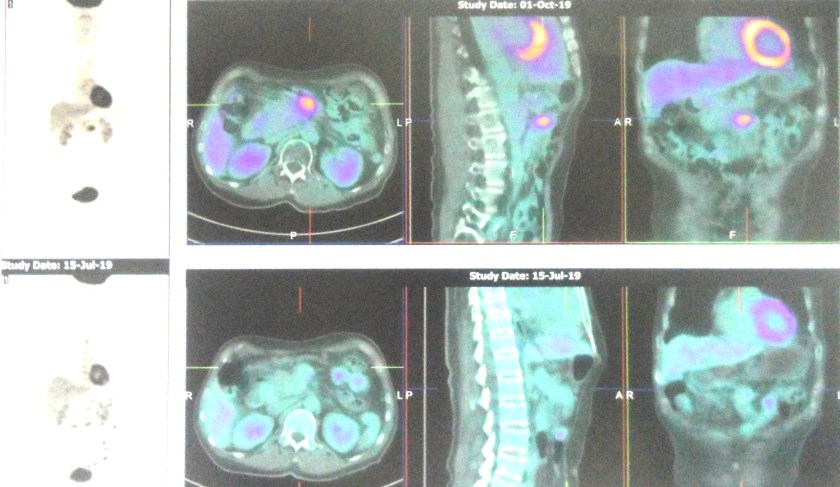

Below are the results of the PET scan done on 1 October 2019 (top row) compared to the one done on 15 July 2019 (bottom row). It is obvious that his cancer did not go away in spite of the treatments given.